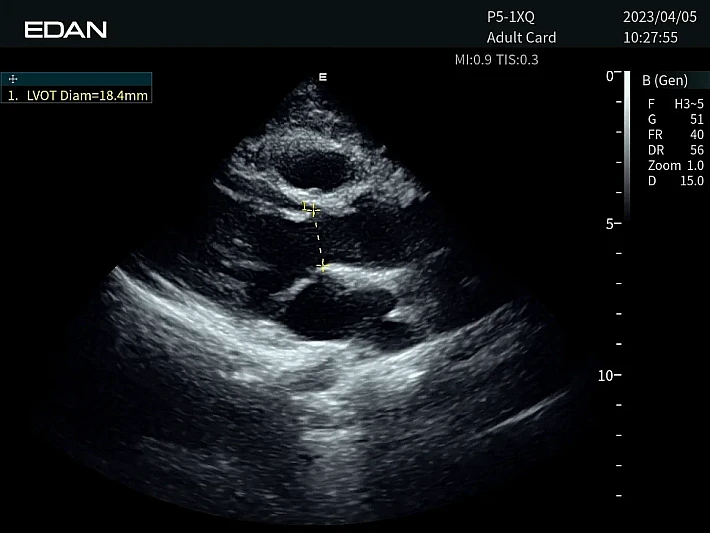

Медицинское оборудование и сервисное обслуживание